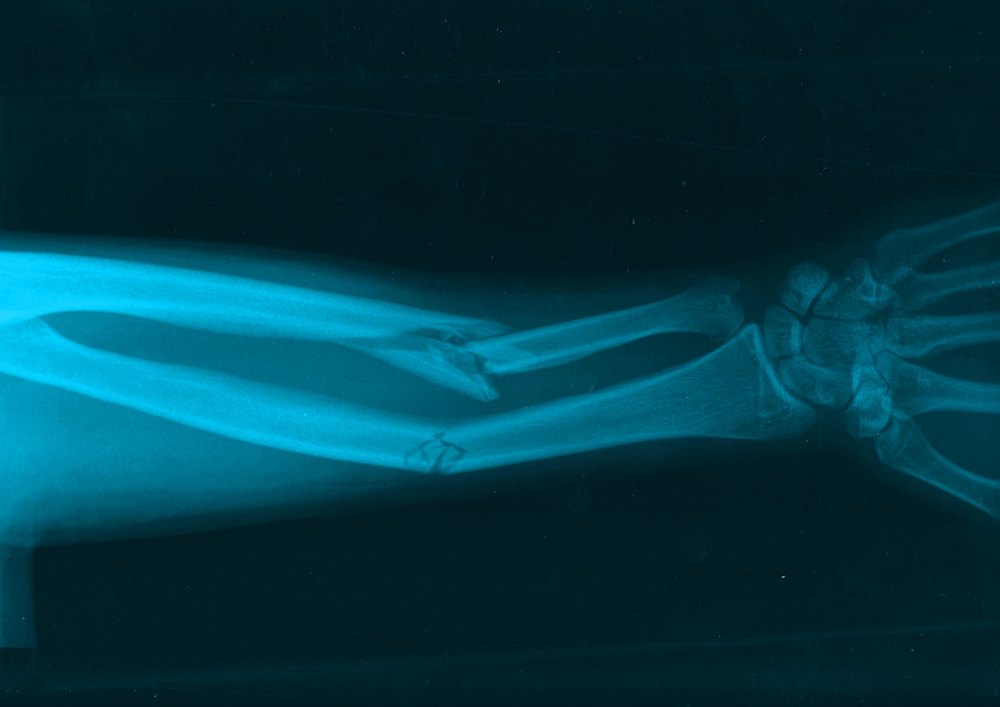

The young woman fell, or was pushed, probably from a significant height. She landed on the palm of her left hand with a force of about 400 pounds per square inch. The violence of that event caused both bones of her forearm (the left ulna and radius) to completely break.

Whoever attended to this injured woman didn’t just engage in palliative care to ensure she was comfortable until she died. That person (or those people) set six wooden splints to stabilize the bones of her left forearm, presumably in the hope that the arm might heal somewhat and retain some functionality. (Morris, the archaeologist, argued this was the first evidence of pre-Columbian surgery in the Americas.) Evidence of a staph infection around the splints indicates she remained alive and well cared for—at least for a time.